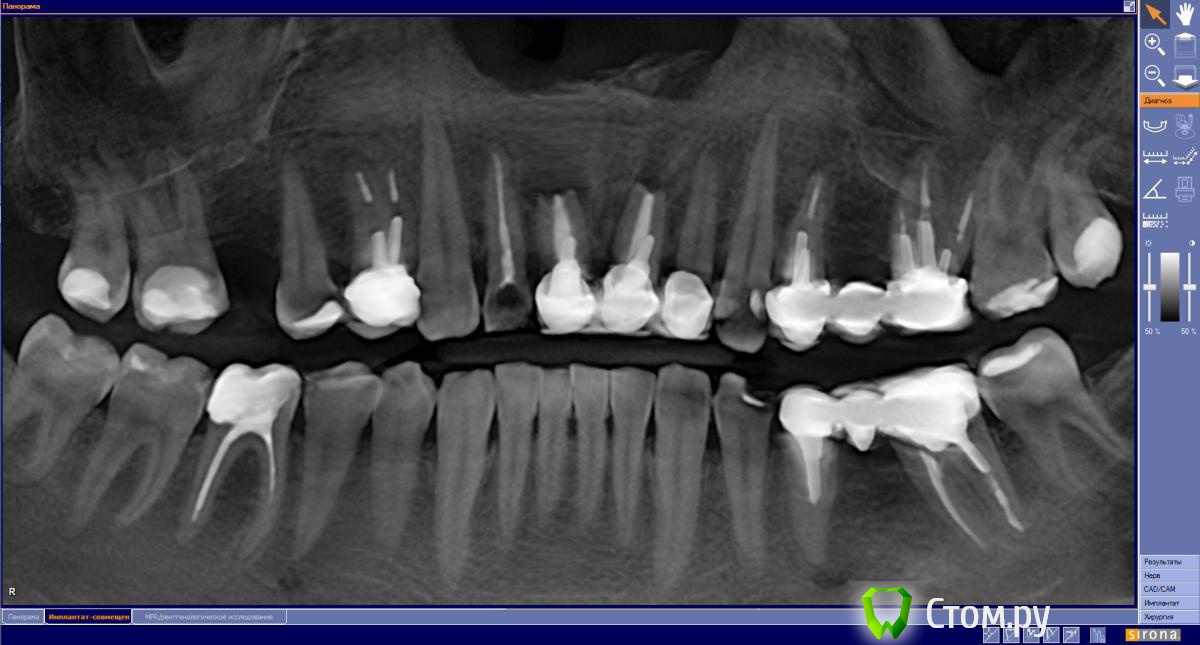

Мне 39 лет 1.1 и 2.1 травма 28 лет назад, повторные кисты после резекции 16 лет назад. Надо удалять, ждать пока нарастет костная ткань и ставит имплантанты. Сколько ждать после удаления для имплантации? Смущает срок 6 мес межу удалением и установкой имплантантов. Действительно так долго?

1.2 надо перелечивать канал или нет?

2.2. депульпировать, надо снимать коронки или можно через коронку?